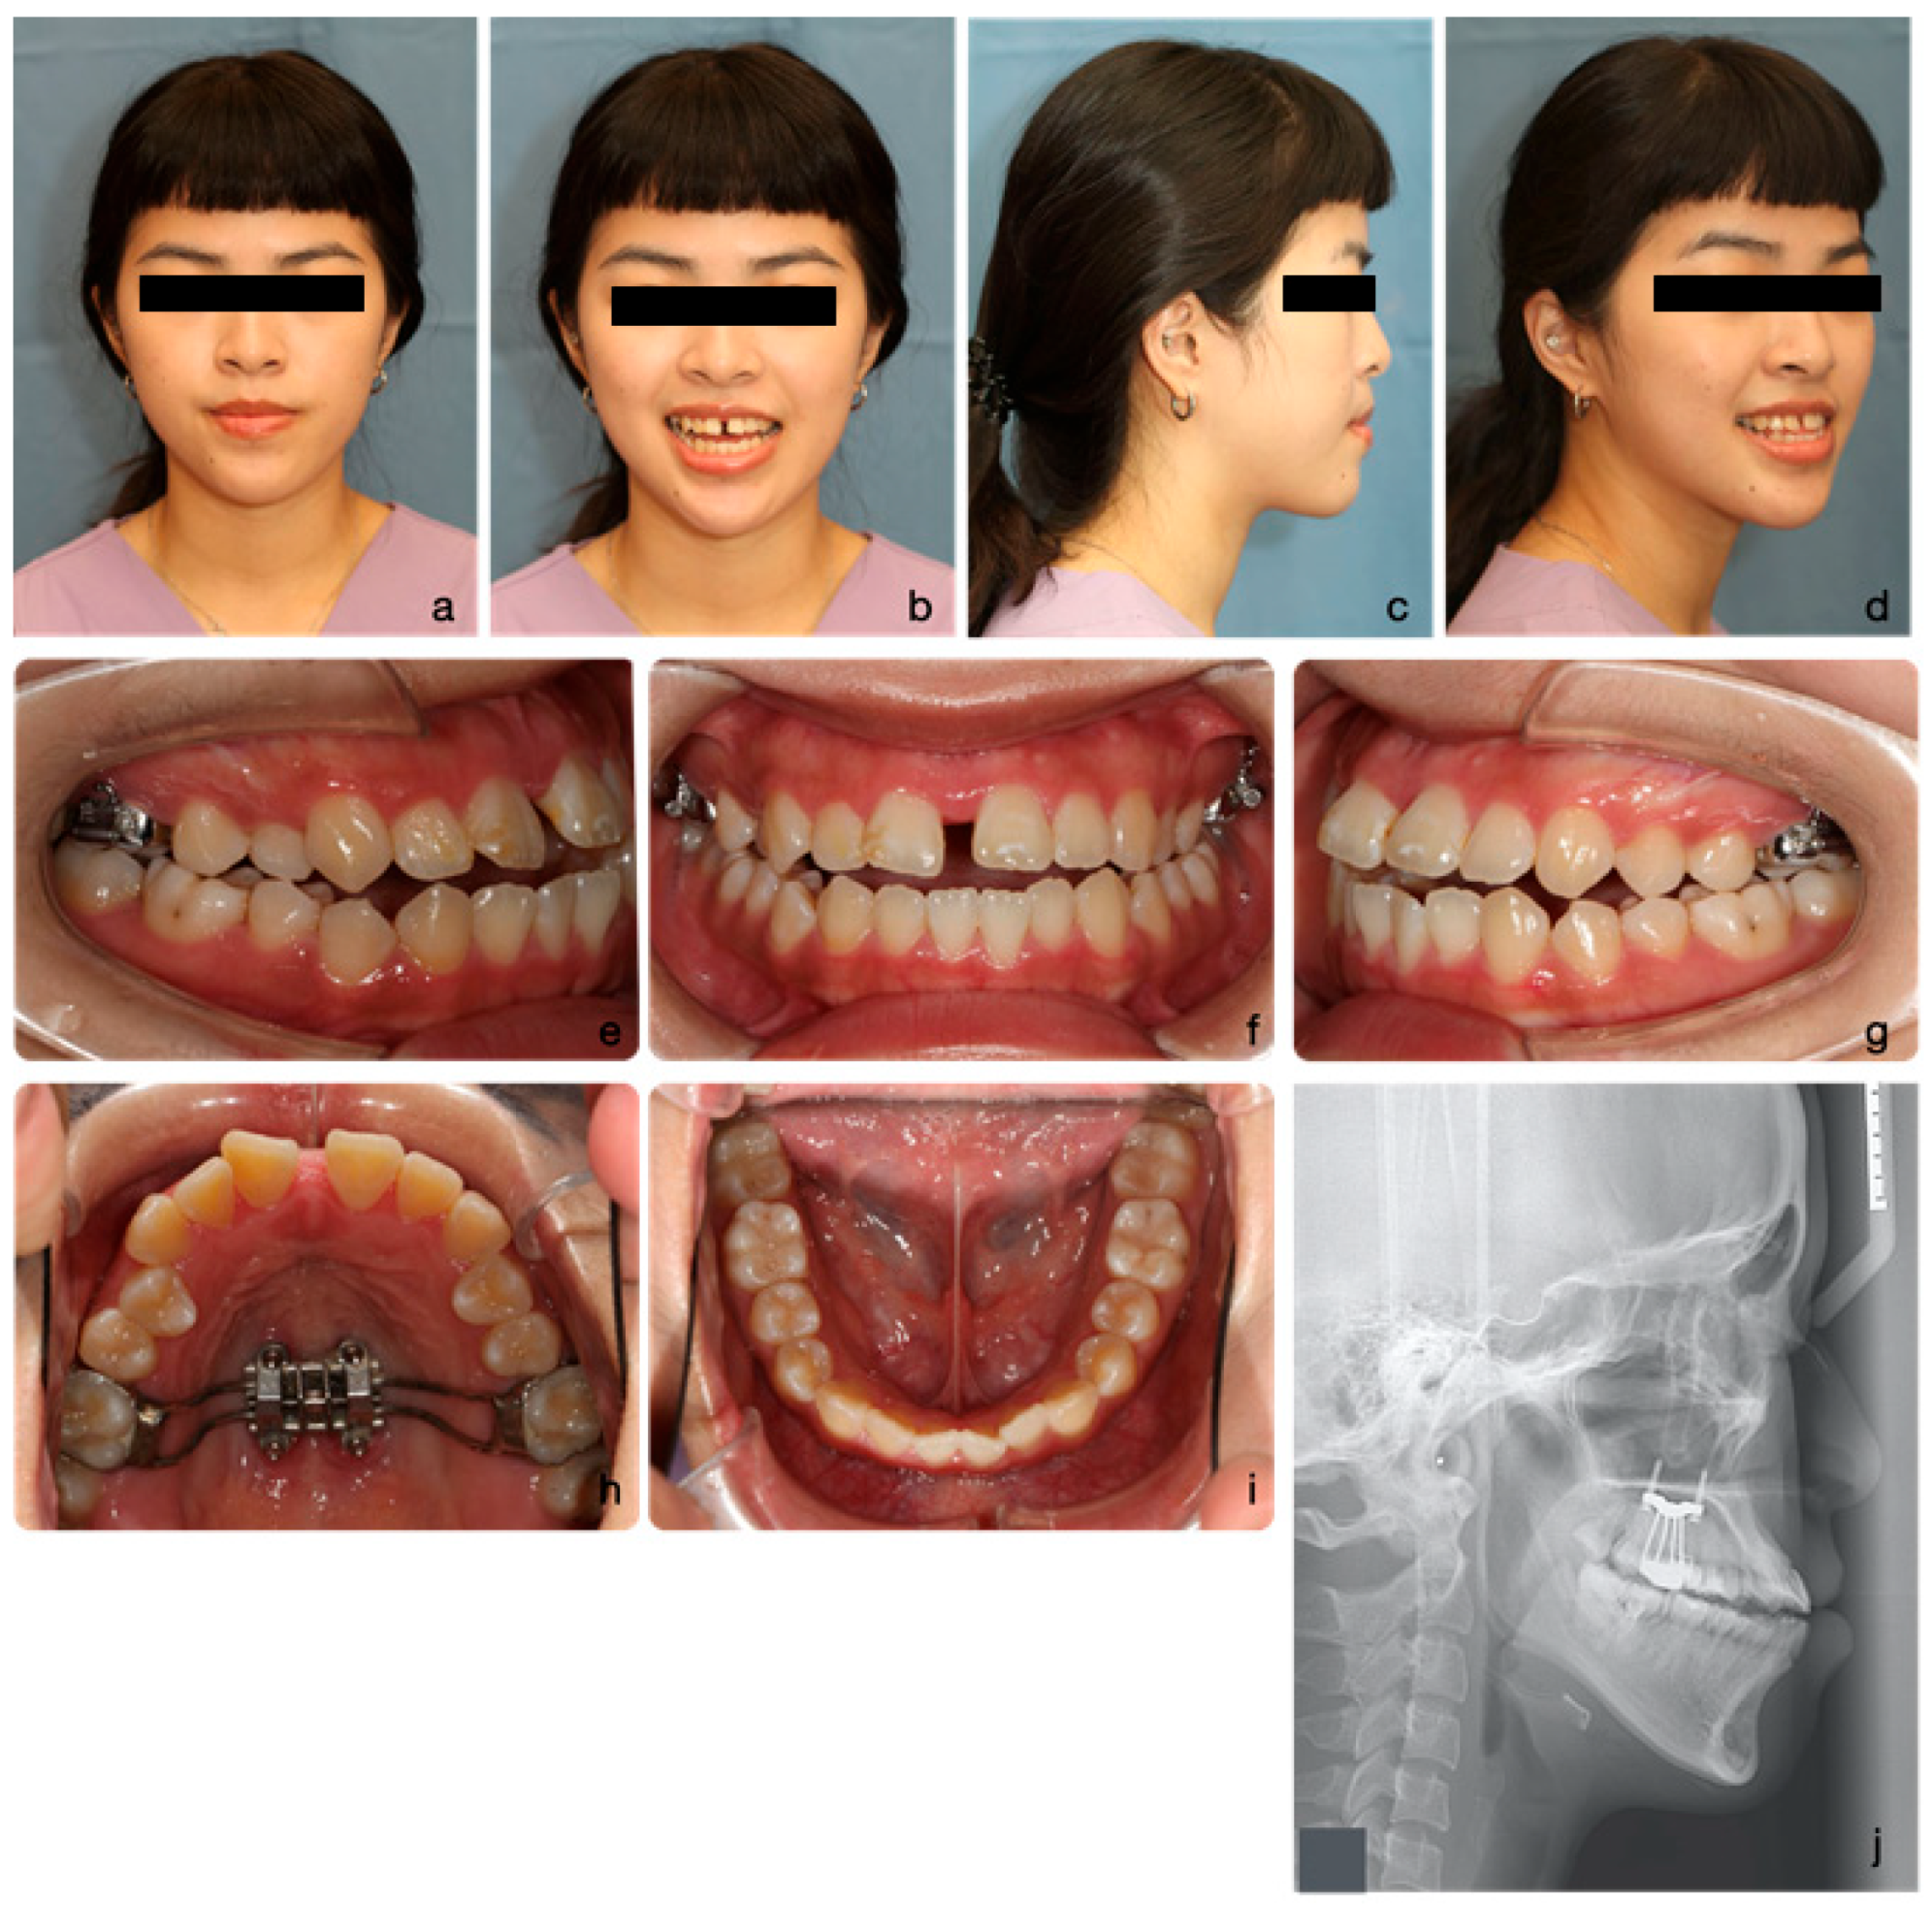

2.4. Treatment Progress

2.5. Treatment Results